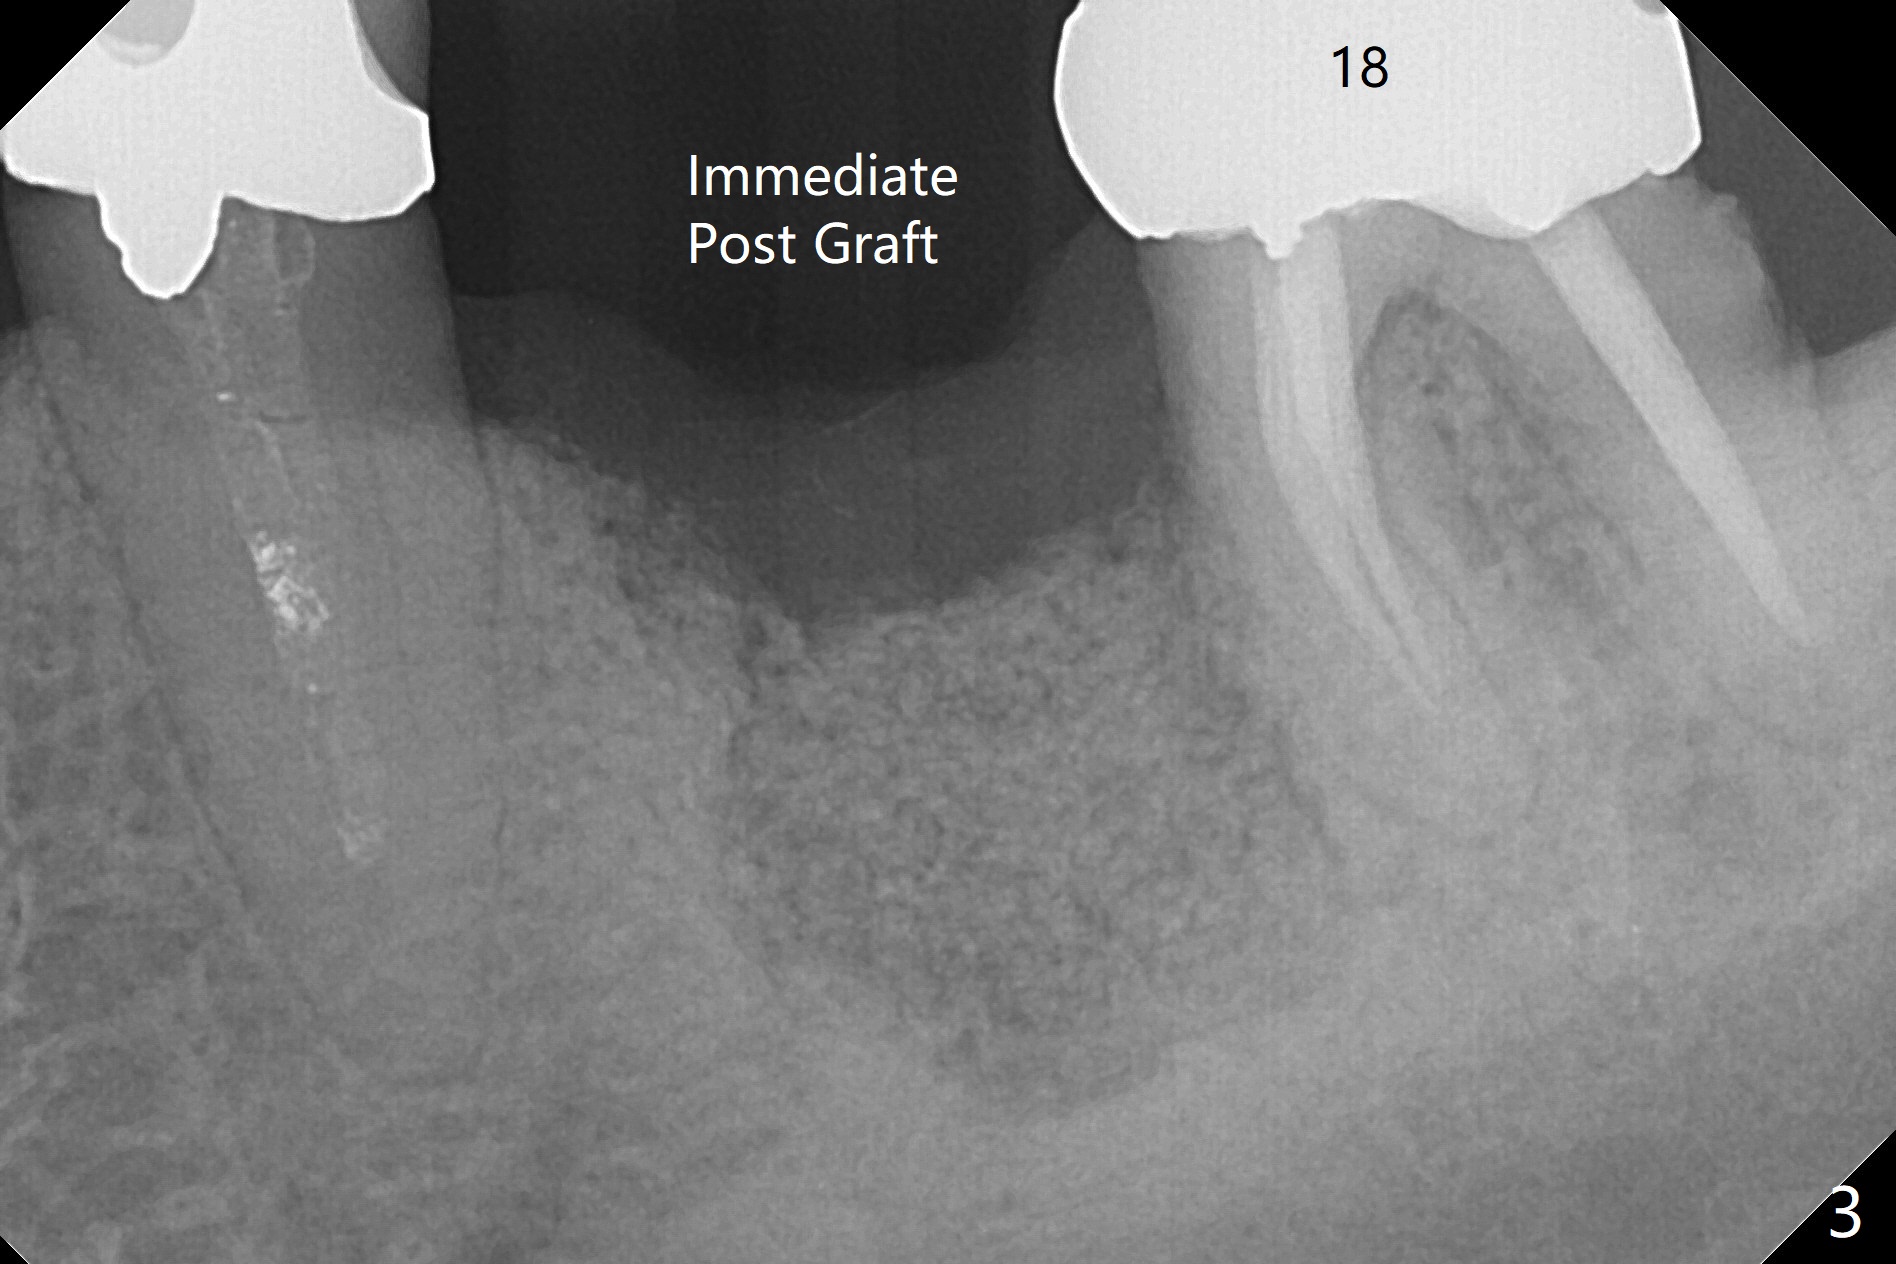

There is calculus formation in the threads of the implant removed (Fig.1), as related to bone loss (Fig.2). Sticky bone is placed, followed by 2 pieces of PRF membranes, 4-0 PGA sutures (Fig.3) and periodontal dressing.